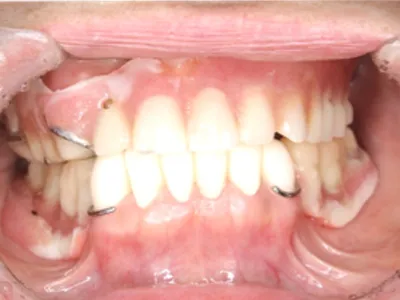

before

主訴入れ歯がくちゃくちゃして噛めない

治療内容被せ物(メタルボンド)保険外の義歯(ミリングギシ)

治療期間1年

費用1,100,000円(税込)(義歯と被せ物代合わせて)

リスク・副作用義歯なので着脱が必要です。仮の義歯を作る場合があります。